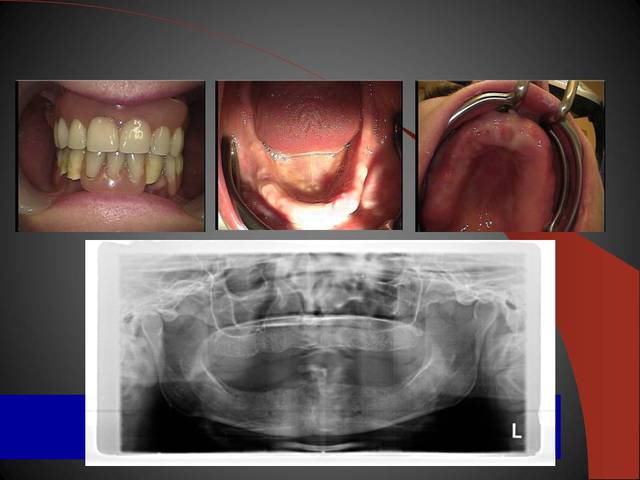

Un cas qui va sans doute prêter à discussions, juste pour montrer que la technique MIMI (non invasive) peut donner des résultats de qualité et esthétiques en moins de temps qu une chirurgie dite traditionnelle.

Les deux premières photos montrent le cas d´une jeune femme ( qui malheureusement s est fait retiré toutes les dents à l´étranger....).Ce cas a pu être terminé deux semaines après l´implantation.

3ème photo: radio d´un patient âgé de 73 ans qui souhaitait avoir des dents fixées.Comme on l´observe il n a plus de place après les foramines mentales.Nous avons donc utilisé juste l´os interforaminal. Nous avons suivi le concept du prof. Nentwig qui consiste à pouvoir ajouter 2 dents dans chaque quadrant dans la mandibule.

Les deux dernières photos montrent le même cas deux ans plus tard.